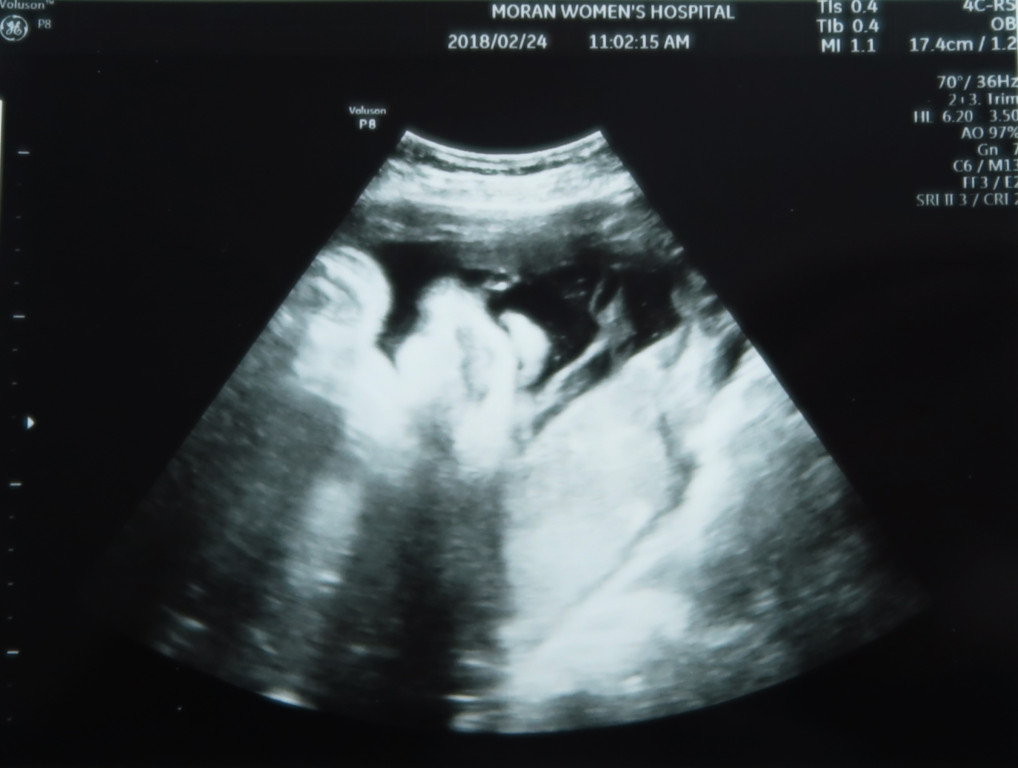

지난 7월에 저희 두 부부 사이에 예상하지 못했던 반가운 손님이 찾아 왔어요~( ๑ ᴖ ᴈ ᴖ)ᴖ ᴑ ᴖ๑)❣

태명은 달이. 별이, 달이 라는 의미도 있고, Moon 대통령 시대에 태어난 아이라 새 시대의 중심이 되길 바라는 마음에^^

몸무게 2.9kg 으로 주수보다 약간 크다고 합니다. 그런데 랑구도 3.8kg이라고 유도분만을 하자고 하셨던 전적이 있는 선생님이라 ㅋㅋㅋ

엄마 뱃속에서 콩알만큼 작은 생명이 우리 가족의 일원이 되었다고 신고하네요~

고 작은 녀석의 심장소리는 또 얼마나 우렁찬지.

서현이 때도 들었던 심장소리지만 또 들어도 마음이 울컥합니다.

1차 정밀초음파 때 (13주) 아빠의 매의눈은 봐 버렸습니다 ( ◥◣_◢◤ )

달이 다리 사이에 무언가 있는것을ㅎㅎ

선생님께 재차 무언가 있는 것이냐 물었지만 선생님은 대답이 없으셨어요ㅋㅋ

재차 삼차 묻는 제가 불편하셨는지 선생님의 눈빛은 흔들리고 ㅋㅋㅋ 그 부위 근처만 가면 다른 곳으로 옮기시던 선생님 (◎-◎;)

2차 정밀 초음파 사진은 얼굴 윤곽만 살짝 나오네요.

그래도 서현이때 보다 얼굴을 덜 가리고 있어서 이런 해골 사진도 남기고 ㅋㅋ

이때는 서현이랑 얼굴이 많이 비슷해 보이네요 ㅎㅎ

콧대는 서현이 보다는 조금 더 있는듯 하나…

이사진은 잠자는 랑구 표정 판박이네요 ㅋㅋ